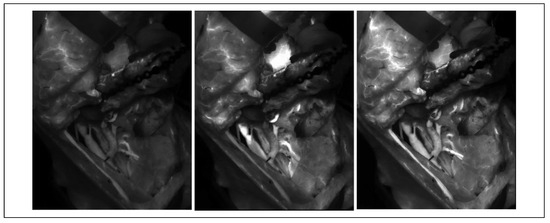

The main outcome variable of this study was perforator free flap perfusion, measured at 3 different time points: (1) immediately prior to division of the pedicle of the free flap from the donor site, (2) after completion of anastomosis, and (3) in the PACU within 60 minutes. SPY quantitatively measured perfusion by taking measurements of fluorescence intensity with an infrared camera, recording the peak perfusion which is considered the difference between the baseline and the peak of fluorescence intensity. This is then translated into a relative and absolute measure of perfusion (Figure 2). Perfusion was measured at 5 points evenly distributed across the free flap with the SPY system, using absolute values. These can range from 0 to 255 absolute perfusion units (APU). For the SPY Elite system, studies have placed a cutoff value of <10 being predictive of flap necrosis.[26] Perfusion was secondarily measured via MAP from the arterial line at these same 3 time points. In the postoperative period, patients were monitored for complications for 4 weeks. Major complications were defined as a flap failure or those with need for intervention in the operating room to salvage the flap. Data were also collected regarding wound healing complications and infections. Complications were qualitatively measured as binary data, either present or not present, with no stratification of severity.

Measurements of perfusion was taken at the skin paddle of the free flap. Relative perfusion was measured in percentages and represented by the colored lines, while the maximum and minimum points of perfusion across the free flap are in absolute units, 125 APU and 22 APU.

Figure 2. Depiction of relative and absolute perfusion measuring flap perfusion.